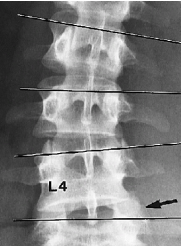

Q what is the name of this measurement? and what is the average + range?

A: Intercrestal Line

assesses the alignment of the L4 body relative to the iliac crests. No average or range is specified.